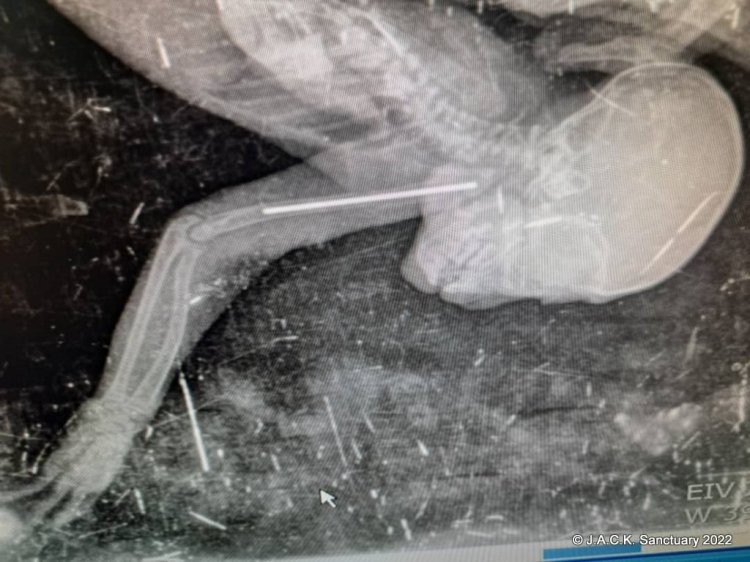

Une radio a été faite au plus vite afin de déterminer la gravité de la fracture de l’humérus. Un chirurgien vétérinaire a donc été appelé en urgence pour opérer le petit singe.

Vu l’âge du bébé et l’épaisseur de son os, le chirurgien a opté pour une broche.